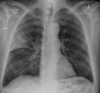

**Heart failure** Alveolar batwing shadowing Kerley B lines Cardiomegaly Upper lobe Diversion Pleural Effusion

4